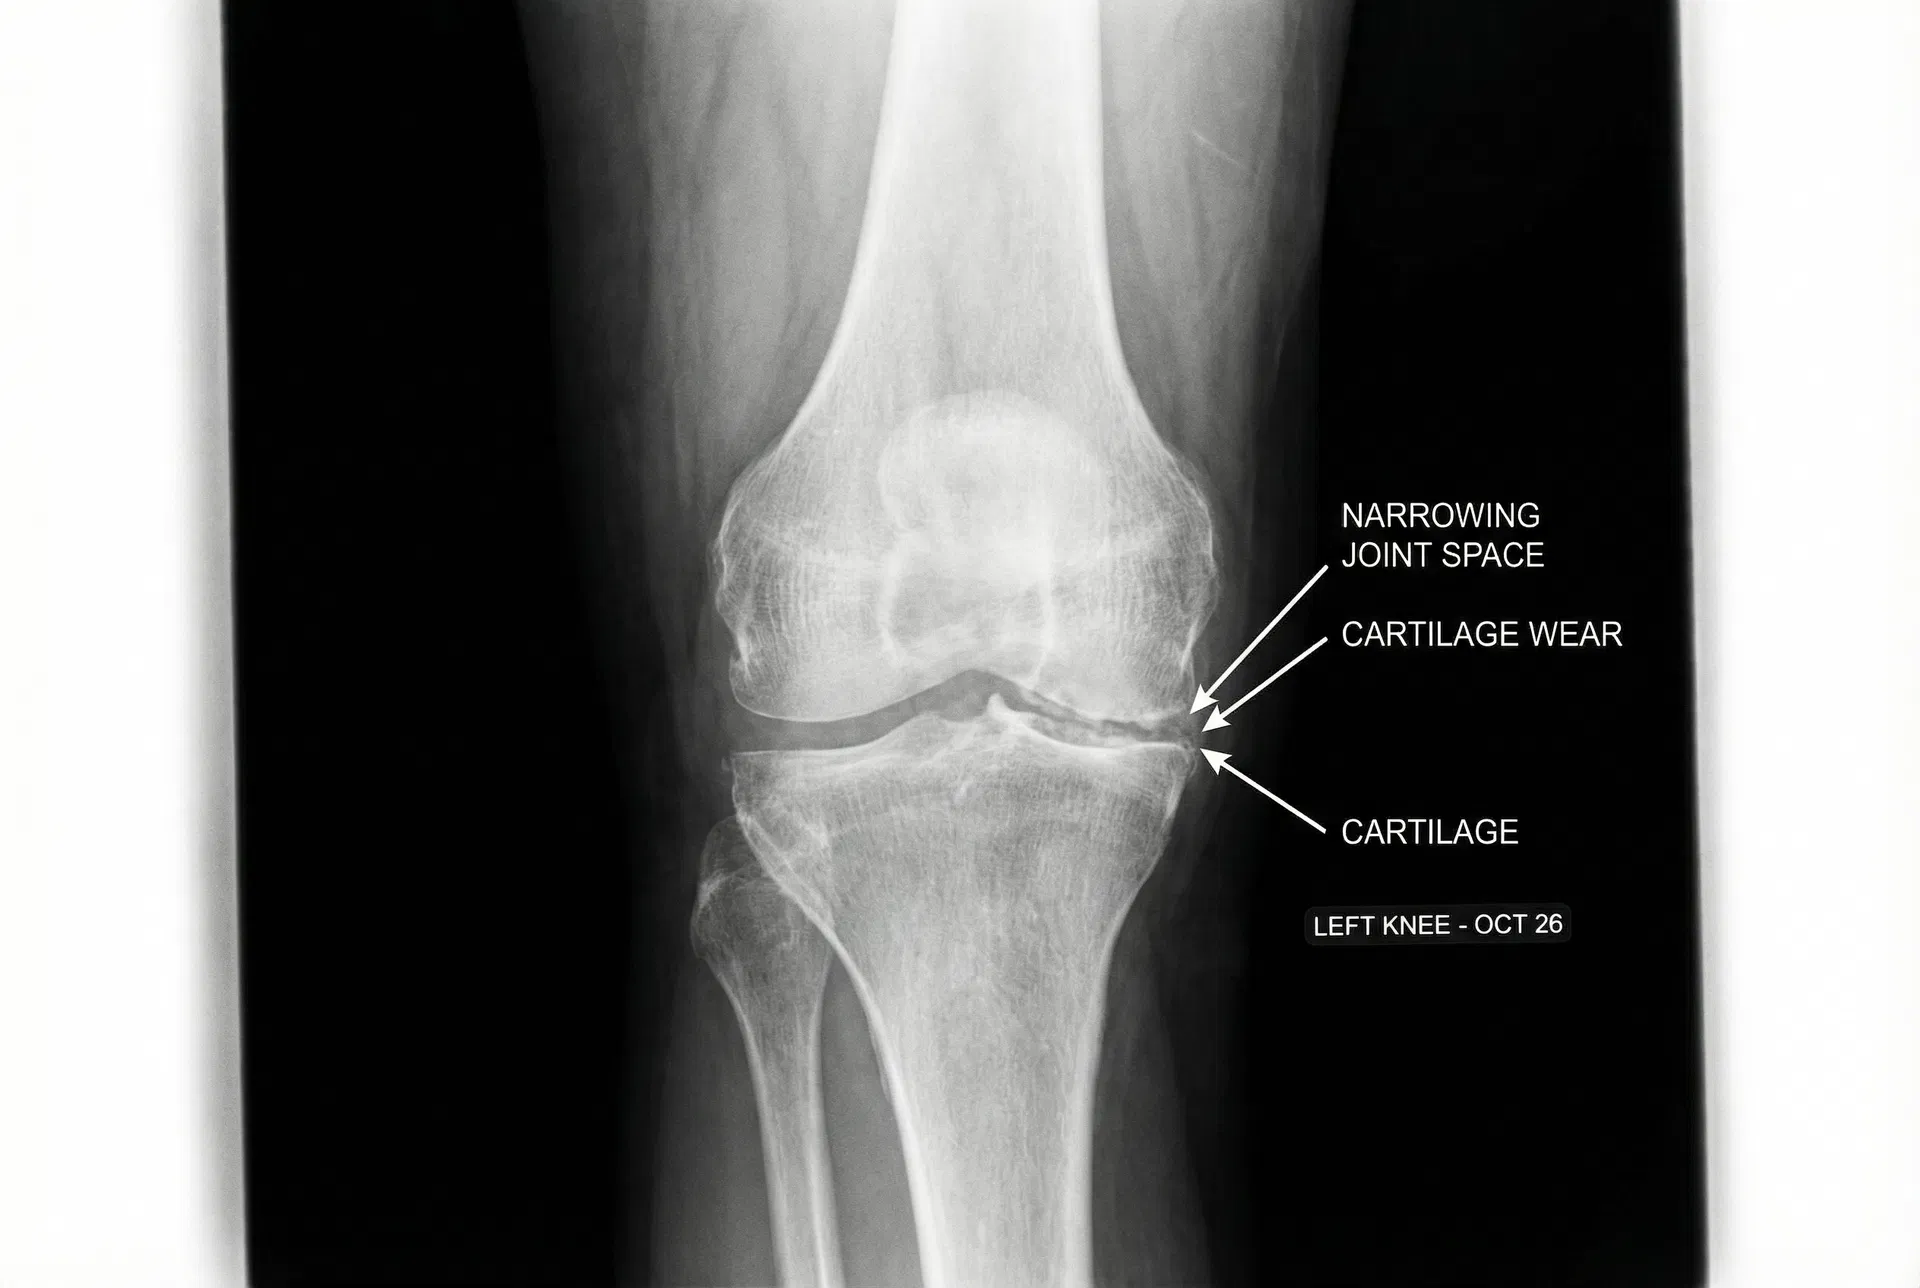

Most people assume joint pain is about cartilage wearing down. That is part of it. But the more immediate cause โ the one that explains why pain gets worse in the morning and improves with movement โ is the depletion of synovial fluid.

Synovial fluid is the lubricant inside your joint capsule. It cushions impact, delivers nutrients to cartilage, and keeps bones from grinding against each other. At 20, you have plenty. By 60, production drops dramatically โ and most joint pain treatments do absolutely nothing to address this.